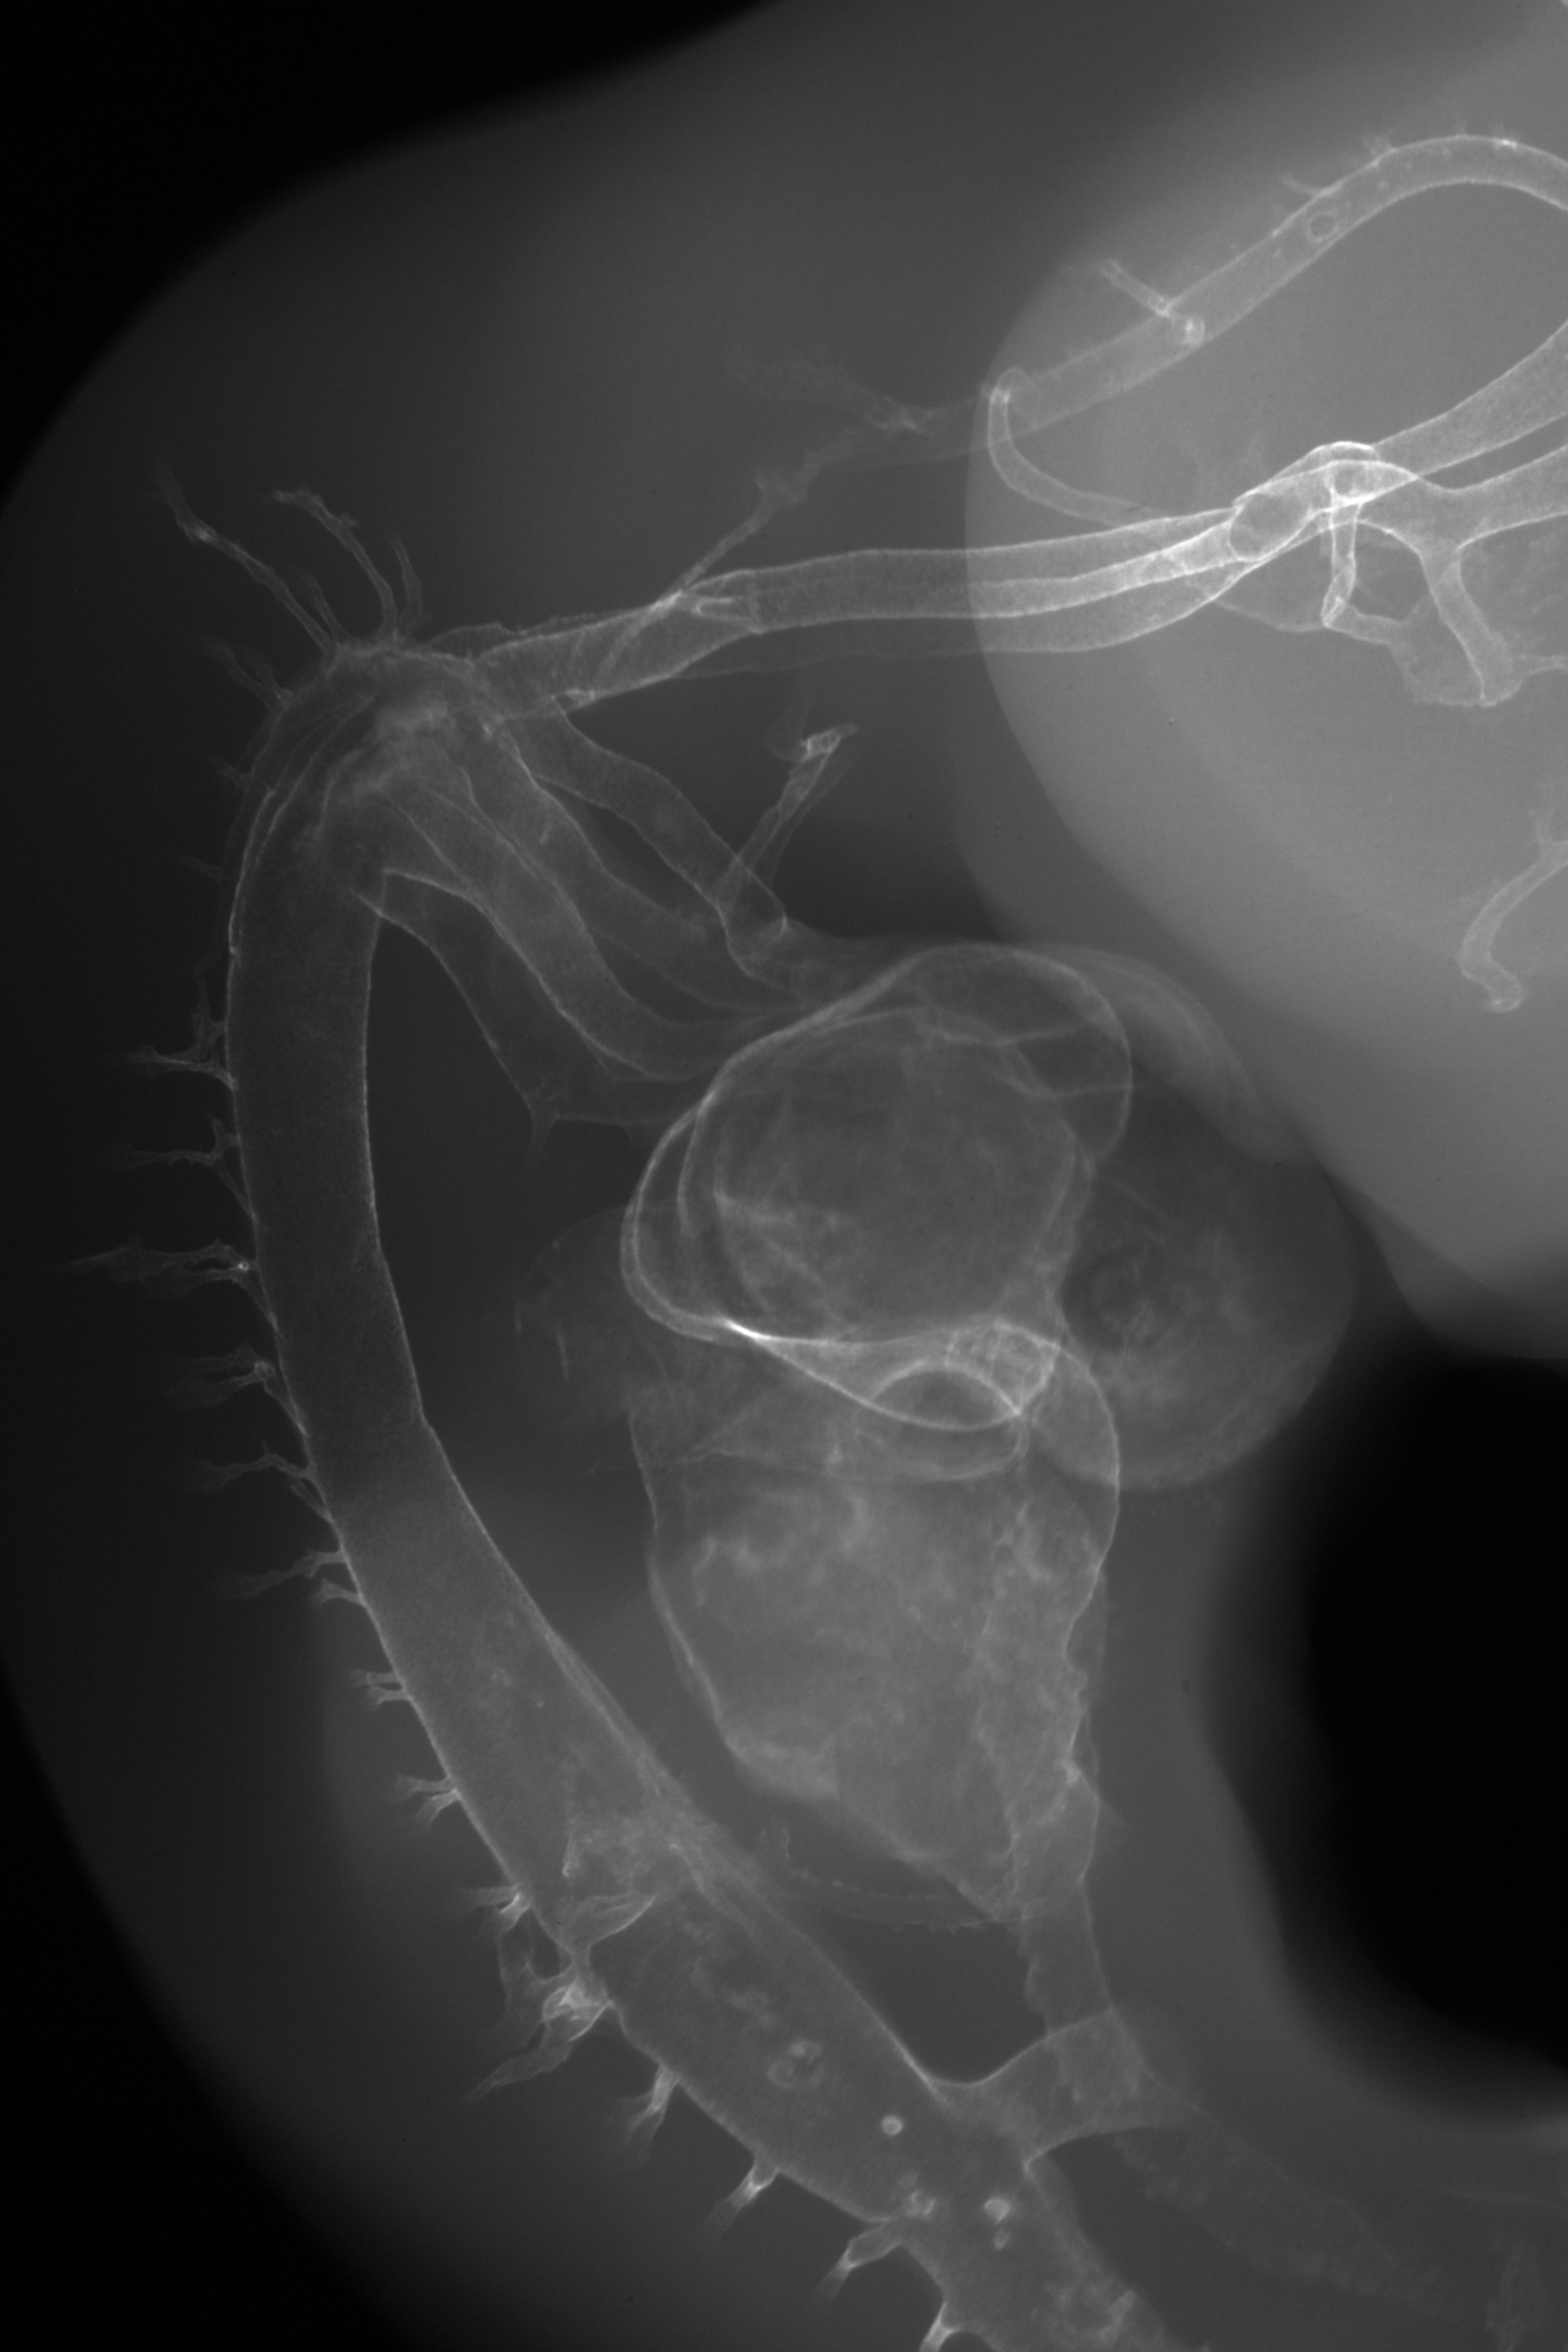

X-Ray Micrographs